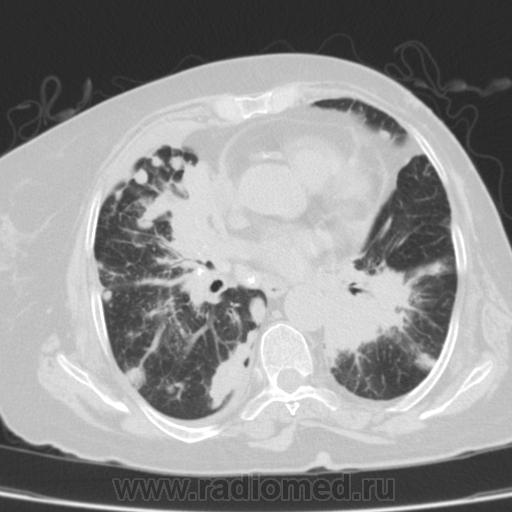

Метастатическое поражение легких.

Пожилая женщина, 76 лет находится на стац.лечении, провели СКТ дообследование.  Сопут- сr левой молочной железы. Такие множественные

поражения  в легких встречаются не часто.

Раннее несколько лет назад оперирована по поводу рака левой молочной железы.

Ну да, неспокойная работа, один тяжелее и  интересней другого. На обзорной рентгенограмме было всё видно прекрасно. Но терапевты направили, а я и не отказалась, чтобы в следующий раз знать- какие они бывают вторичные поражения легких.